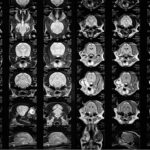

El equipo de Hospital Canis tiene una gran experiencia y formación en neurología y neurocirugía, además de tener a nuestra disposición los equipos más avanzados como es la Resonancia Magnética.